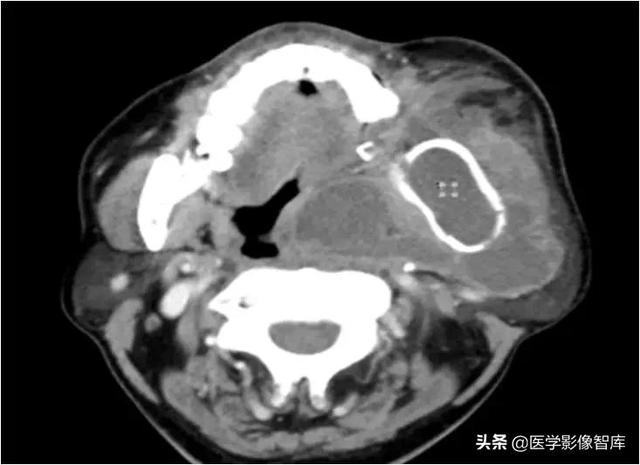

咀嚼肌间隙、颌下间隙、左侧颞下间隙,颊间隙,翼颌间隙

男,55岁,左下后牙反复肿疼1年余,加重1月余,疼痛剧烈伴张口受限,面部肿胀。

咀嚼肌间隙有脓肿形成。